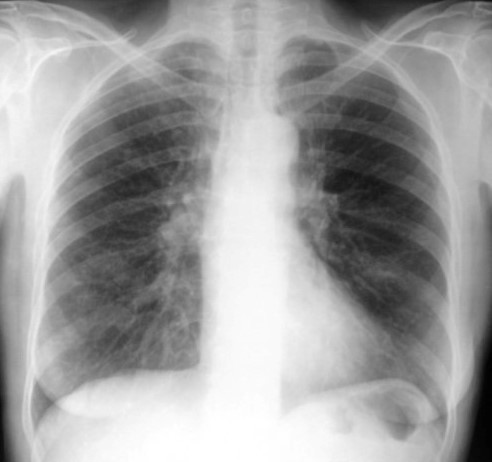

Vous faites réaliser un électrocardiogramme ainsi qu’une radiographie pulmonaire que voici :

Question 1 : Interprétez la radiographie pulmonaire :

Pas d’anomalie parenchymateuse, pas de pneumothorax, pas d’épanchement pleural

– radiographie pulmonaire normale, excluant notamment les diagnostics différentiels :

pas de signe de surcharge,

pas de foyer de pneumopathie,

pas de pleurésie ou pneumothorax.

radiographie pulmonaire le plus souvent normale éliminant ainsi les diagnostics différentiels pulmonaire (pneumopathie, pleurésie) et cardiaque